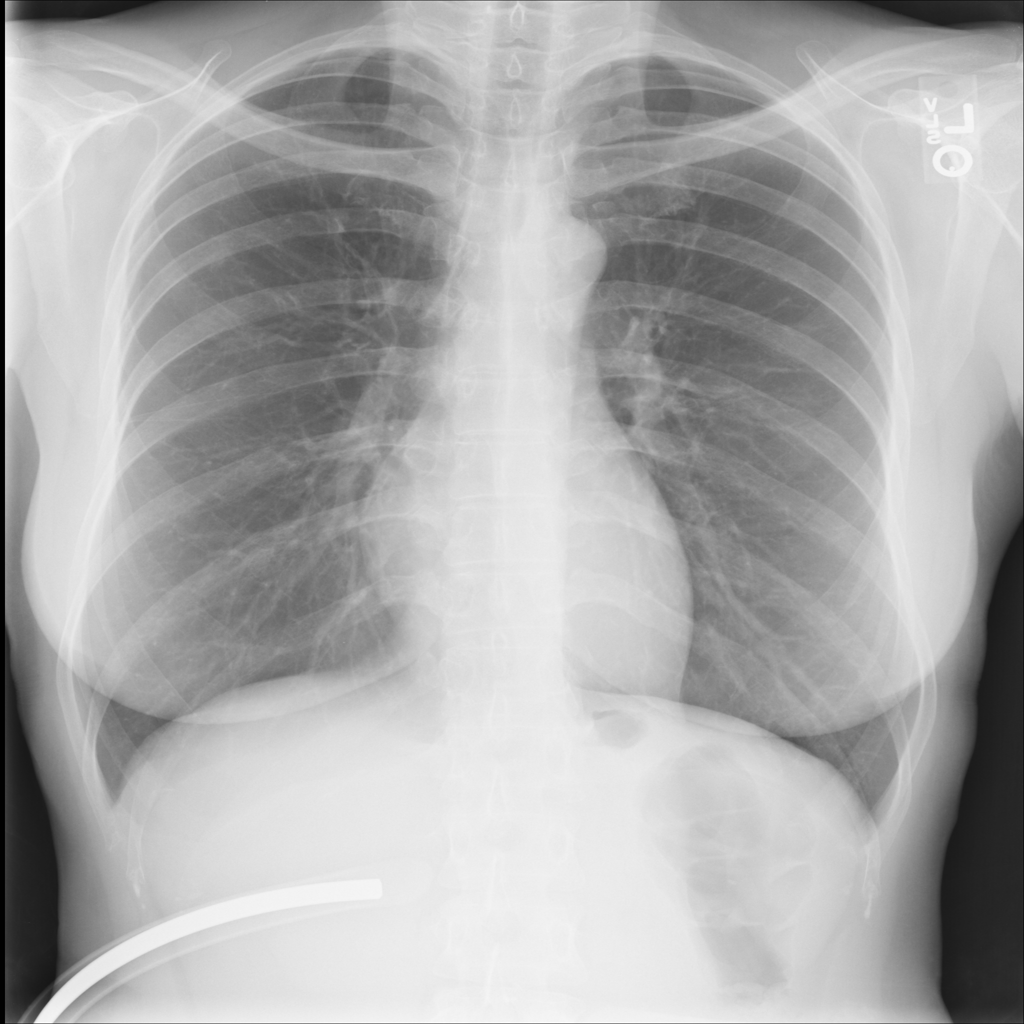

PAT-EBE1 · IMG-019Pneumonia

PAT-EBE1 · IMG-019

AP